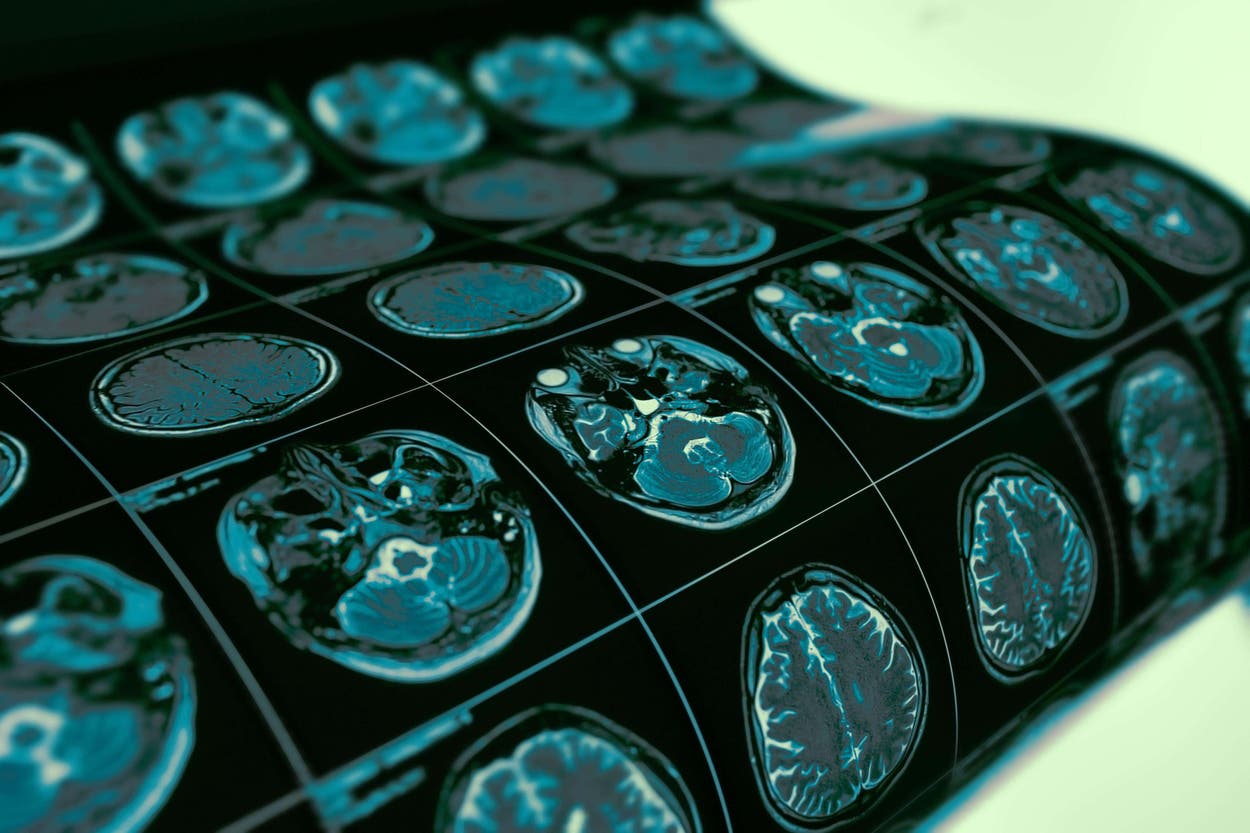

I had brain #MRI scan last Thursday looking for recurrent #glioblastoma (&/or treatment complications). I found out yesterday that there is still no sign of recurrence. I couldn’t be happier!!!!!

El lunes escribió en X para informar que la semana pasada se había sometido a una resonancia magnética y que seguía sin signos de recidiva.